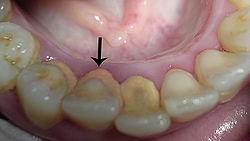

De tandsteen kan ook op of onder de tandvleesrand gaan zitten waardoor het tandvlees ontstoken kan raken. Tandsteen is poreuzer dan tandglazuur, waardoor het gemakkelijker verkleurt.

Tandsteen ontstaat doordat het calcium en fosfaat in het speeksel in de tandplaque gaat zitten. Die tandplaque verhardt zich dus. Er zijn twee soorten tandsteen: subgingivaal en supragingivaal tandsteen. Subgingivaal tandsteen is tandsteen dat onder het tandvlees zit. Supragingivaal tandsteen zit boven het tandvlees op de tand of kies.

Tandsteen ontstaat het snelst bij de uitgang van speekselklieren, bijvoorbeeld vlak achter de ondertanden.